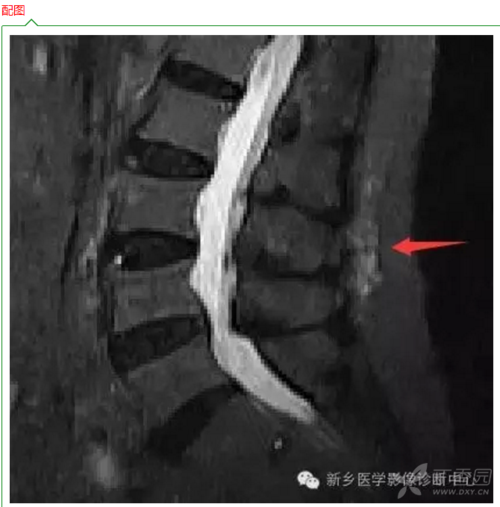

腰肌劳损核磁共振图片

腰肌劳损核磁共振图片,腰椎间盘突出水肿图片

大家给我看看这是拍的腰椎磁共振帮我看看有问题吗,医生说腰肌劳损

教你用磁共振看腰肌劳损(转载)

19:41:03 男,31岁,体型瘦(170,56kg),长期坐着工作,有慢性腰肌劳损